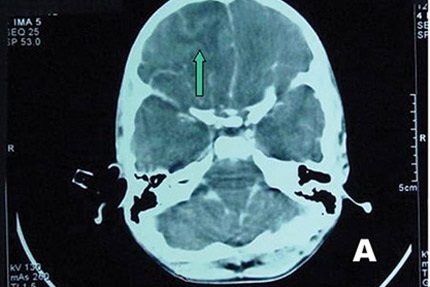

Tại BV Bệnh Nhiệt đới, BN sốt 39oC, lơ mơ, cổ cứng, thở nhanh 30 lần/phút. Kết quả xét nghiệm soi dịch não tủy không thấy có vi trùng lao hay vi nấm gây viêm màng não nhưng lại có sự hiện diện của một loại amip.

Sau khi anh T. tử vong, BV Bệnh Nhiệt đới tiếp tục làm nhiều xét nghiệm và kết quả xét nghiệm sinh học phân tử PCR cho thấy anh tử vong do “amip ăn não người” tấn công.